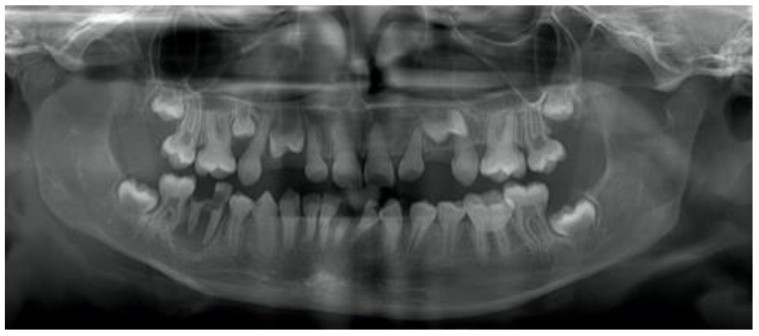

7. (Select ONE OR MORE correct answers)

The 13-year-old healthy boy presents with discomfort from lower right. What is/are the most likely diagnosis/es for tooth 4.5?